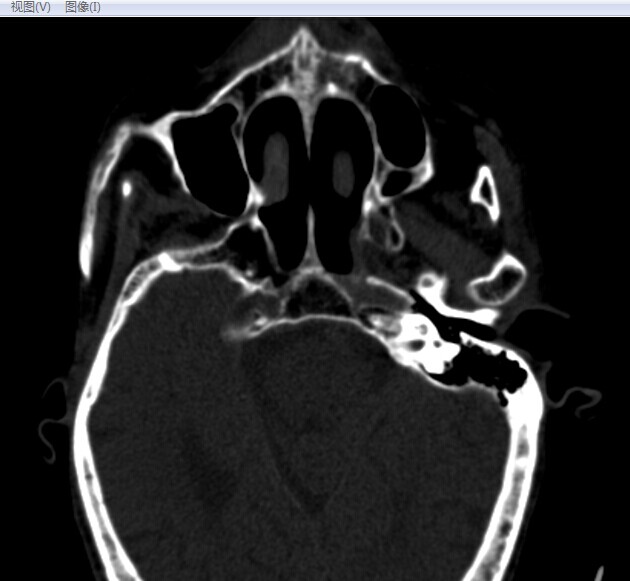

CT49621:咽喉CT

F85,吞咽、咬合无力,家人述因扁桃腺肿大治疗约10天。

喉前庭缩小,右侧咽隐窝扩大,左侧咽隐窝缩小甚至消失。

考虑喉部淋巴癌

软组织增厚 境界清晰 考虑淋巴瘤